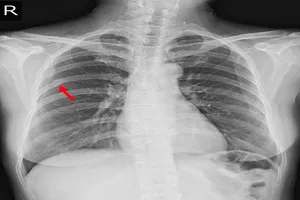

2. 폐렴, 폐색전증

폐에 염증이 생기는 폐렴이나 폐혈관에 혈전이 생겨 막히는 폐색전증과 같은 질환은 가슴 통증을 유발할 수 있습니다. 이러한 질환들은 가슴 통증 외에도 기침, 호흡곤란, 열 등의 증상을 동반하기도 합니다. 정확한 진단을 위해 흉부 X-ray, CT 촬영 등의 영상 검사와 객담 검사를 시행하며, 항생제 투여, 산소 요법 등 질환에 맞는 적절한 치료를 받아야 합니다.